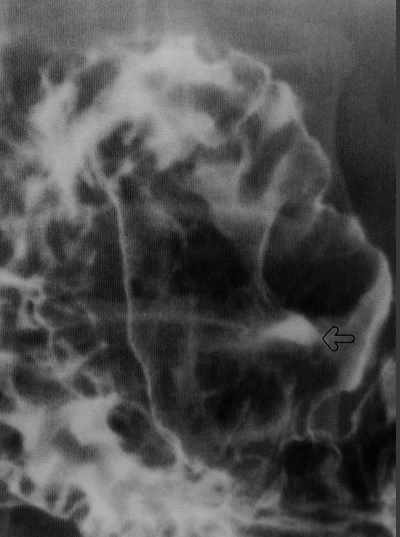

Pathologies bénignes du tube digestif